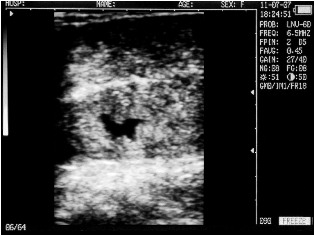

Cow with calf. Deadline - 25 days